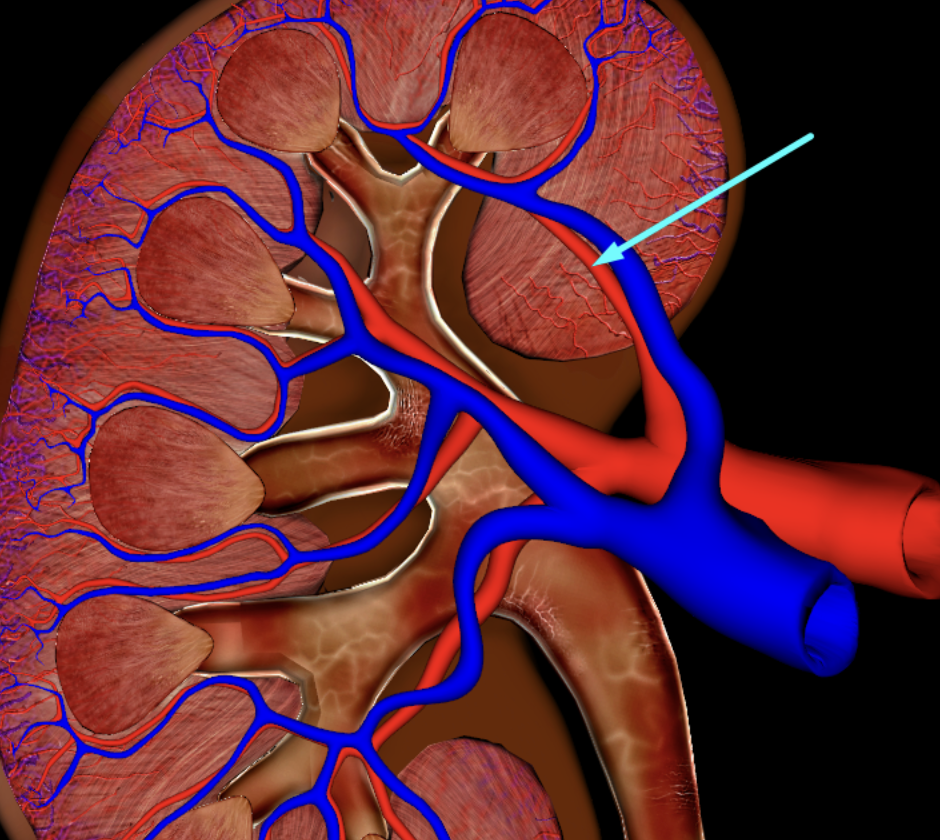

green: renal hilum

yellow: ureter

red: abdominal aorta

green yellow and red

interlobular vein

segmental artery

interlobar vein

arcuate artery